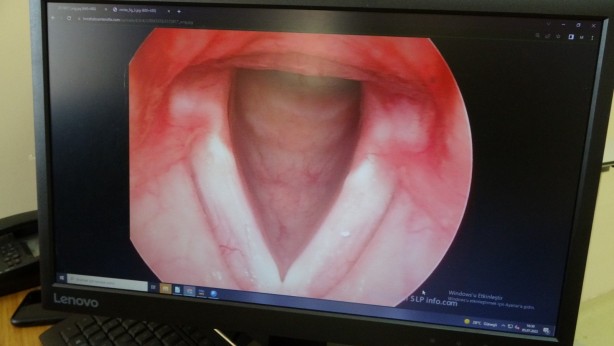

Sigara kullanımı insanlarda birçok olumsuz etkiyi beraberinde getiriyor. Çeşitli hastalıkların yanı sıra sigara kullananlarda ses kısıklığı da meydana gelebiliyor. Bu problem nedeniyle seste kalınlaşma, sesin cızırtılı gelmesi, sesin kolay yorulması, boğuk ve zor duyulur bir ses gibi belirtiler görülebiliyor. Zarar gören ses tellerinde poliplerin ve ödemlerin oluşmasıyla meydana gelen ses kısıklığı nedeniyle ileri safhalarda nefes darlığı ve konuşmakta ciddi güçlükler de oluşabiliyor. Bu rahatsızlığı geçiren kadınlarda ise ses kalınlaşması oluşabiliyor. Hastalar, seslerinin erkek sesi gibi kalın olmasından ve telefonda konuştukları kişinin kendilerini erkek sanmaları gibi nedenlerden dolayı hastanelere başvurabiliyor. Oluşan bu rahatsızlık ise kısa süren bir ameliyat ile tedavi edilebiliyor.

“Sigara ses telinde yaptığı hasarlara bağlı olarak ses kısıklığı yapabilir” Doç. Dr. Enver, “Sigaranın ses tellerine olumsuz etkileri saymakla bitmez. Bunlar arasında gırtlak kanseri ve nefes darlığı gibi pek çok şey var. Ama bunların yanı sıra kansere neden olmadan da sigara ses telinde yaptığı hasarlara bağlı olarak ses kısıklığı yapabilir. Ses kısıklığı özellikle kadınlarda ses telindeki sigara poliplerine, sigara ödemlerine bağlı olur. Bu erken dönemde ses kısıklığı gibi problemlere neden olurken, zamanın geçmesiyle bu poliplerin büyümesiyle, sigaranın etkisiyle nefes darlığı ve konuşmakta ciddi güçlüklere neden olabilir. Bu hastalar genelde seslerinin kalın olmasından ve telefonda kendilerine beyefendi diye hitap edilmesinden dolayı bize başvururlar. Yaptığımız muayenede ses telindeki sigara polibini gördüğümüz zaman genelde ameliyat kararını alırız. Ameliyat ağız içerisinden ses telindeki polibin çıkartılması işlemine dayanıyor ve boğazda, boyunda herhangi bir kesiğe gerek kalmıyor. İşlem sırasında sesi kaybetmek gibi bir risk yok. Hastalarımız sıklıkla bize bunu sorarlar. Ses ameliyattan hemen sonra iyileşmeye başlıyor. Genelde hastalarımızın beş ile yedi gün kadar hiç konuşmamalarını isteriz. Sonrasında hastalarımız seslerini yeniden kullanmaya başlarlar. Sesin gerçek haline, en güçlü haline ulaşmasıysa birkaç ay sürer. Çünkü ses telinin iyileşmesi zaman alır” dedi.

“Ameliyattan sonra eğer hasta sigara içmeye devam ederse bu durum tekrarlayabilir” Doç. Dr. Necati Enver, “Bu duruma sebep olan en temel şey sigara. Sigara aynı zamanda bu problemlere de neden oluyor. Sigaranın dışında boğaz reflüsü, diğer ismiyle gırtlak reflüsü de ses tellerinde bu gibi değişikliklere neden olabilir. Ameliyattan sonra eğer hasta sigara içmeye devam ederse bu durum tekrarlayabilir ve tekrarlayan ameliyatları yapmak hem bizim için hem de hastamız için daha zorlu olacaktır. Hastalarımızın ameliyattan önce sigarayı bırakmasını istiyoruz. Bu sayede ses tellerinin daha iyi iyileşmesi sağlanabilir. Standart ses teli polibi ameliyatlarına göre daha detaylı ve hassas çalışmayı gerektiren bir ameliyat olması nedeniyle iyileşme biraz zaman alabiliyor. Ameliyattan bir hafta sonra hasta sesini kullanmaya başlasa da ameliyattan sonraki iyileşme süreci iki ila dört ay sürmekte. Ve bu sürenin sonunda ses tamamen normale dönebilmektedir. Hastalar ameliyat oldukları günün akşamında sıklıkla evlerine gidebiliyorlar. Ameliyattan sonra herhangi bir ağrı kesici kullanmalarına hemen hemen hiçbir zaman gerek kalmıyor. Ameliyat hasta açısından aslında çok kolay bir işlem. Ama bizim açımızdan mikroskop altında çalışılan çok ince bir iş. Çünkü ses telleri bir parmak boğumu büyüklüğünde çok küçük bir doku. O gördüğümüz polipler de bir veya iki mercimek tanesi büyüklüğünde. Aslında çok küçük bir hastalıktan bahsediyoruz. Ama çok kritik bir yerde olduğu için mikroskop altında çok ince çalışmamız gerekiyor” dedi.